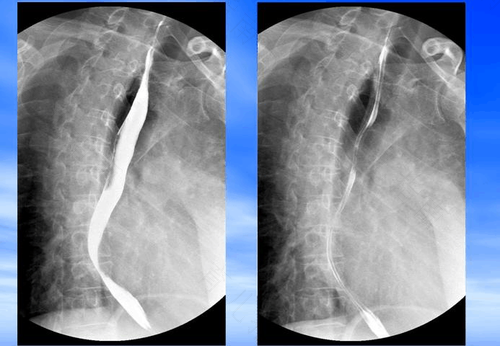

上消化道造影在检查过程中,患者需要吞入造影剂,这样才能方便进行检查,而且能够帮助医生更加清楚的看到患者消化道内的微小病变,相对来说检查结果是比较准确的,检查部位包括患者的口咽部、食管部、胃部和十二指肠等,可以让患者更加详细的了解自己的健康状况。

上消化道造影可以帮助患者发现疾病存在,例如食道癌等,发现了疾病存在,患者才能及时做好预防和治疗,以免疾病发展严重。在进行上消化道造影检查时,患者需要空腹进行,一般在前一天晚上十点过后就不要吃东西了,包括水也不能吃。